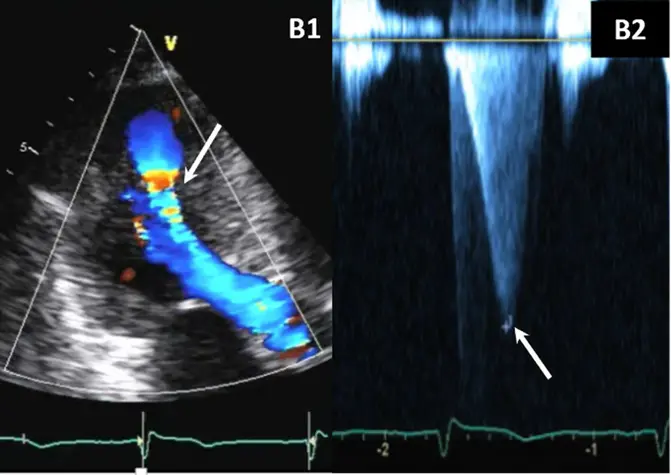

- Color-flow Doppler shows turbulence at mid-ventricular level

- CWD typically shows a narrow, late-peaking systolic velocity (“ice pick” appearance)

- combined LVOT and MVO